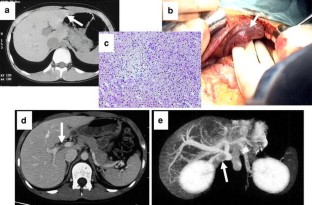

Patent ductus venosus (PDV) is a rare condition, which usually presents secondary to hepatic atrophy and hepatic failure. We have treated eight cases of PDV, all with hypergalactosemia and hyperbilirubinemia. Ultrasonography and three-dimensional computed tomography demonstrated communication between the portal vein and the inferior vena cava. Of the eight PDV cases, three from the older age group (ages 9, 11, and 14 years) had high-density lesions in their brain nucleus, and one case (age 19 years) had undergone prior Kasai portoenterostomy for biliary atresia. Six PDV patients underwent ligation of PDV and the remaining two cases underwent partial banding of PDV with intraoperative monitoring to maintain portal vein pressure (PVP) under 30 cm H2O. Improvement of the intrahepatic portal vein flow was achieved by ligation or banding of PDV. Postoperatively, serum galactose and bilirubin fell to normal ranges, but portal thrombus occurred postoperatively in the first case. We subsequently administered postoperative anticoagulation in the remaining cases and experienced no major complications. These results suggest that PDV ligation and banding are effective surgical approaches for patients with PDV. Close postoperative monitoring to avoid portal thrombus is imperative in these cases.

Fig. 1